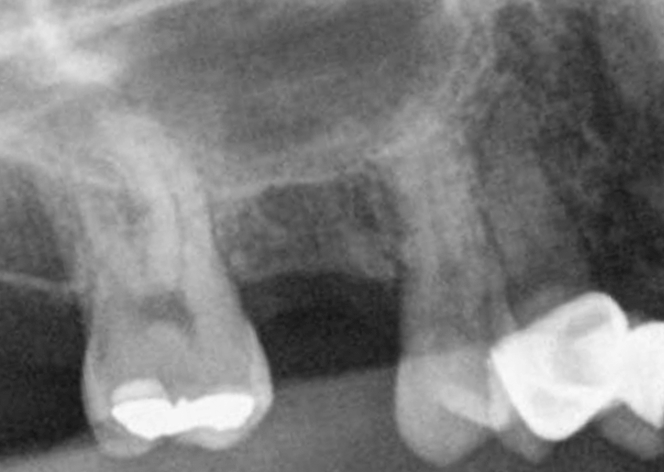

La panoramica dimostra l’esiguità del triangolo retrocanino che non può pertanto essere utilizzato per l’inserimento di due impianti. L’area posteriore rivela un’atrofia ossea pronunciata che richiede un rialzo di seno con innesto di osso del paziente (autologo) che verrà prelevato dal ramo mandibolare